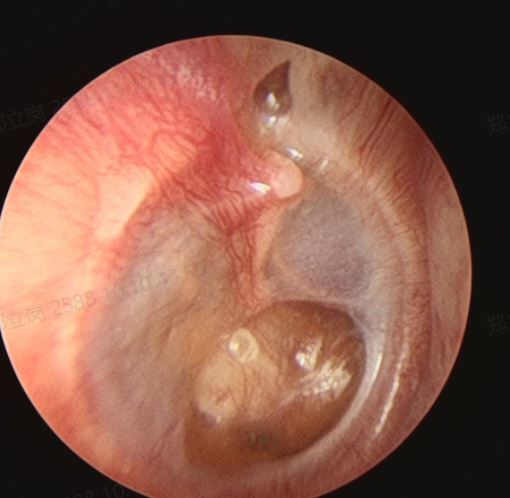

来自广东佛山顺德的刘女士,由于体检发现右侧鼓膜内陷,听力下降,当地医生建议捏鼻子鼓气,但是坚持了几个月没多大效果。最后听说佛山复星禅诚医院耳鼻喉治疗这种情况比较专业。就找到耳鼻喉郑立岗医生,检查后发现李女士是粘连性中耳炎,听力有下降,建议做耳内镜微创手术。

考虑后李女士及时入院了,这次做的是全麻耳内镜粘连性中耳炎微创手术,在耳内镜下不用做任何的体表切口,直接翻起外耳道鼓膜皮瓣,完整翻起内陷的上皮组织后发现听骨链是完整,活动可。取合适大小的耳屏软骨加强鼓膜,整个的手术非常的顺利,持续约60分钟。术后查房患者无明显的不适,无手术相关的并发症。